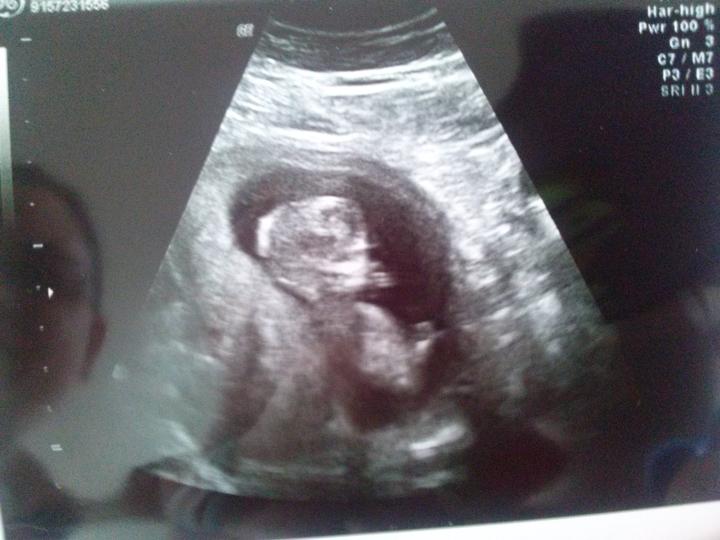

Dnes 25 dl Tp teď uz vím, ze to bude dřív , ale cítím se čím dal lepší, tak uvidíme , kdy se princezně bude chtit na svět , všichni jsme v pohotovosti , takže jsem úplně v klidu 🙂